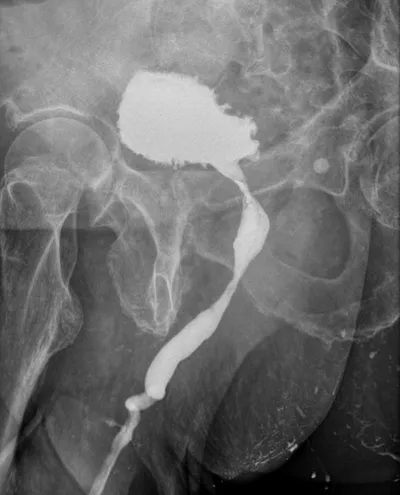

L'hystérosalpingographie est un examen prescrit habituellement dans les cas de stérilité, d'avortements spontanés à répétition, de troubles des règles ou de saignements anormaux.

Il permet à l'aide de l'instillation locale d'un produit de contraste de mieux connaître la forme de l'utérus et de détecter des anomalies : fibromes, polypes ou adhérences.

L'hystérosalpingographie trouve toute son utilité dans l'analyse morphologique et fonctionnelle des trompes : perméabilité, rétrécissement, obstructions, séquelles d'infections.